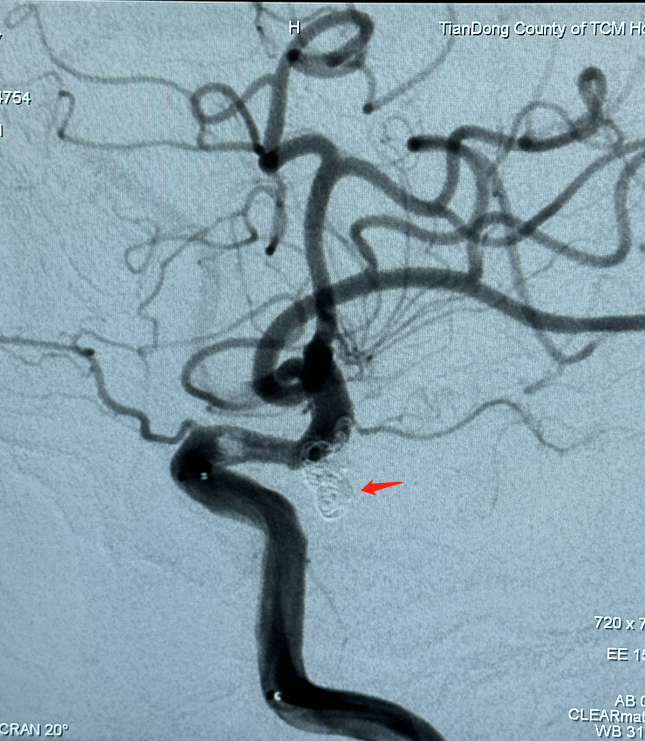

家住平马镇,65岁的言爷爷因突发头晕呕吐3小时到田东县中医医院脑病科住院治疗,行头颅CT扫描检查结果提示“蛛网膜下腔出血”,为患者进一步行脑血管造影检查时发现了一枚“不定时炸弹”一右侧颈内后交通宽颈动脉瘤(4.0*6.0mm)。动脉瘤累及了重要血管分支,极容易破裂出血。

行血管造影术精确动脉瘤大小

我院脑病科团队与右江民族医学院第一附属医院黄建敏主任团队对患者病情进行积极的术前讨论,考虑为破裂颅内动脉瘤,与患者及家属商议后决定行介入治疗。于7月25日为患者在全麻下行介入治疗——经导管支架辅助颅内动脉瘤弹簧圈栓塞术。